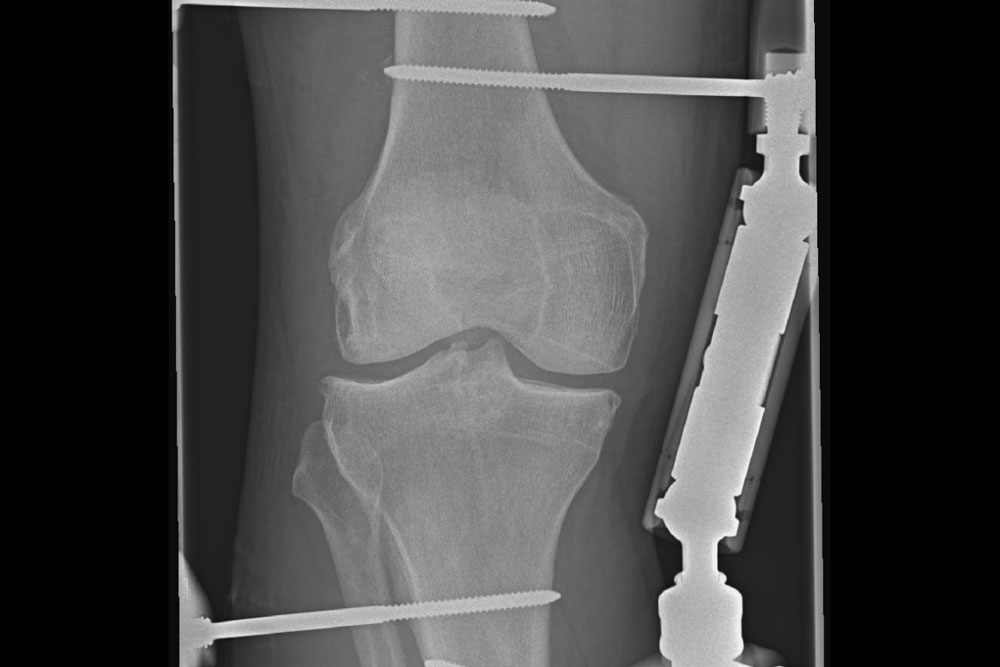

Wenn die Voraussetzungen erfüllt sind, wird der KneeReviver© in einem operativen Eingriff am Oberschenkel- und Unterschenkelknochen fixiert. Der zweitägige stationäre Eingriff erfolgt geplant und unter sicheren medizinischen Bedingungen.

3. Phase der Gelenkdistraktion

Nach der Anlage beginnt die sechswöchige Distraktionsphase. Das Kniegelenk wird mindestens 5 mm auseinander gezogen, wodurch die Gelenkflächen entlastet werden. Der Patient kann das operierte Bein in Streckung vollständig belasten. Auf Grund der Streckstellung erfolgt eine Thromboseprophylaxe. Es erfolgen regelmäßige ärztliche Kontrollen, mindestens nach einer und drei Wochen. Bei Patienten mit weiter Anreise kann eine ärztliche Kontrolle auch vor Ort erfolgen.

4. Entfernung des Systems & Wiederaufnahme der Beweglichkeit

Nach Abschluss der Distraktion wird das Gerät in einem eintägigen stationären Aufenthalt wieder vollständig entfernt. Vor Ort wird eine bildgebende Kontrolle (Röntgen / DVT) durchgeführt, um den Zustand des Kniegelenks zu beurteilen. Im Anschluss beginnt die Phase der schrittweisen Wiedererlangung der Beweglichkeit durch eigenständige Übungen als auch durch begleitende physiotherapeutische Maßnahmen. Der zeitliche Verlauf ist individuell unterschiedlich und beträgt in der Regel etwa sechs bis zwölf Wochen.